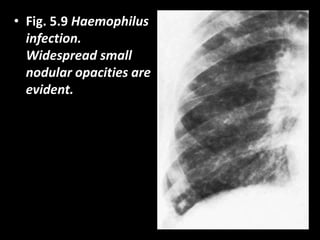

• Fig. 5.9 Haemophilus

infection.

Widespread small

nodular opacities are

evident.

• Fig. 5.9Haemophilus infection. Widespread small nodular opacities are evident.